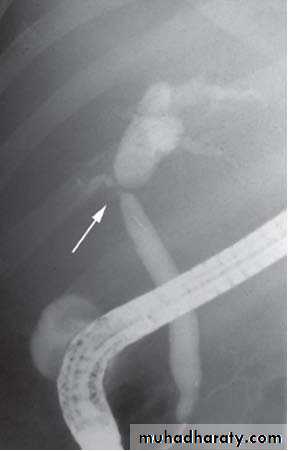

Endoscopic retrograde cholangiopanreatography (ERCP)

Side veiwing endoscopieCannulation of ampulla of Vater

Injection of contrast to visualize the bile ducts

Endoscopic sphincterotomy

Extraction of stone by Dormia basket or balloon catheter

Some times stent placement